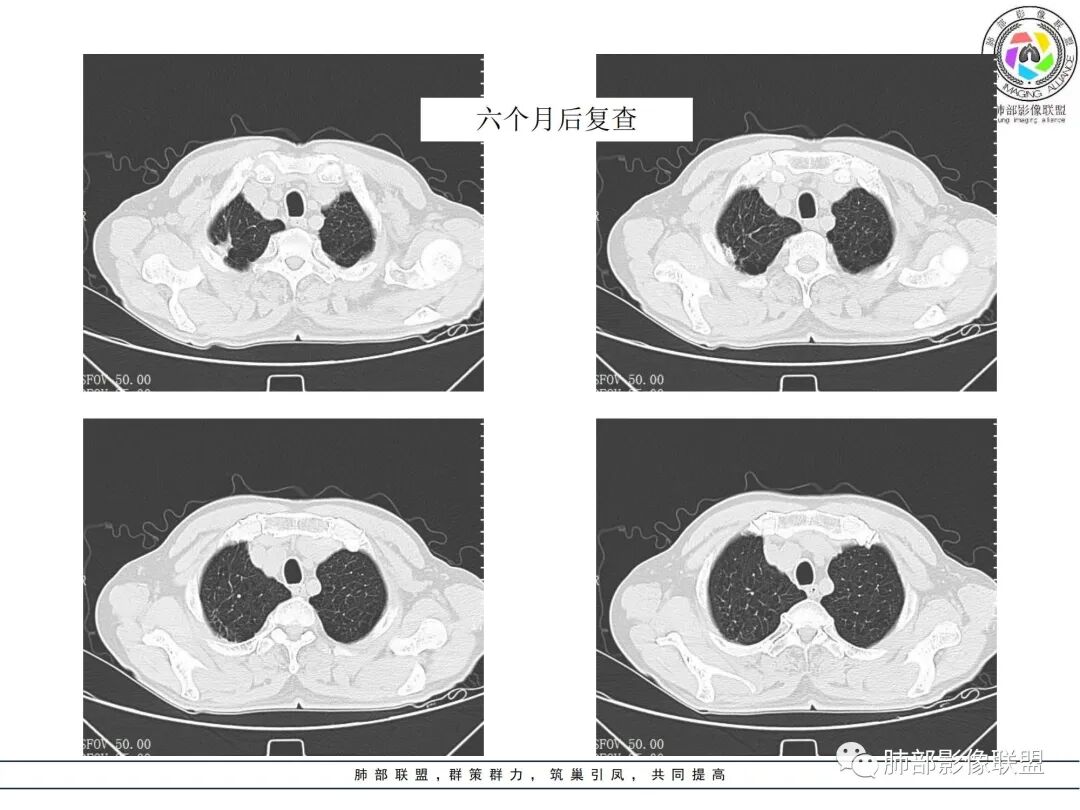

治疗前后对比CT:

放线菌病